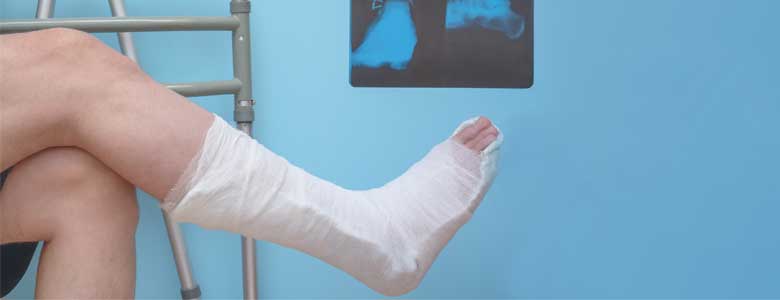

Fracturas

Dr. Tranquilino Carlos - Fracturas Caídas, golpes con un objeto, torcerse o doblarse el hueso son algunas de las causas más normales de fracturas. Más información